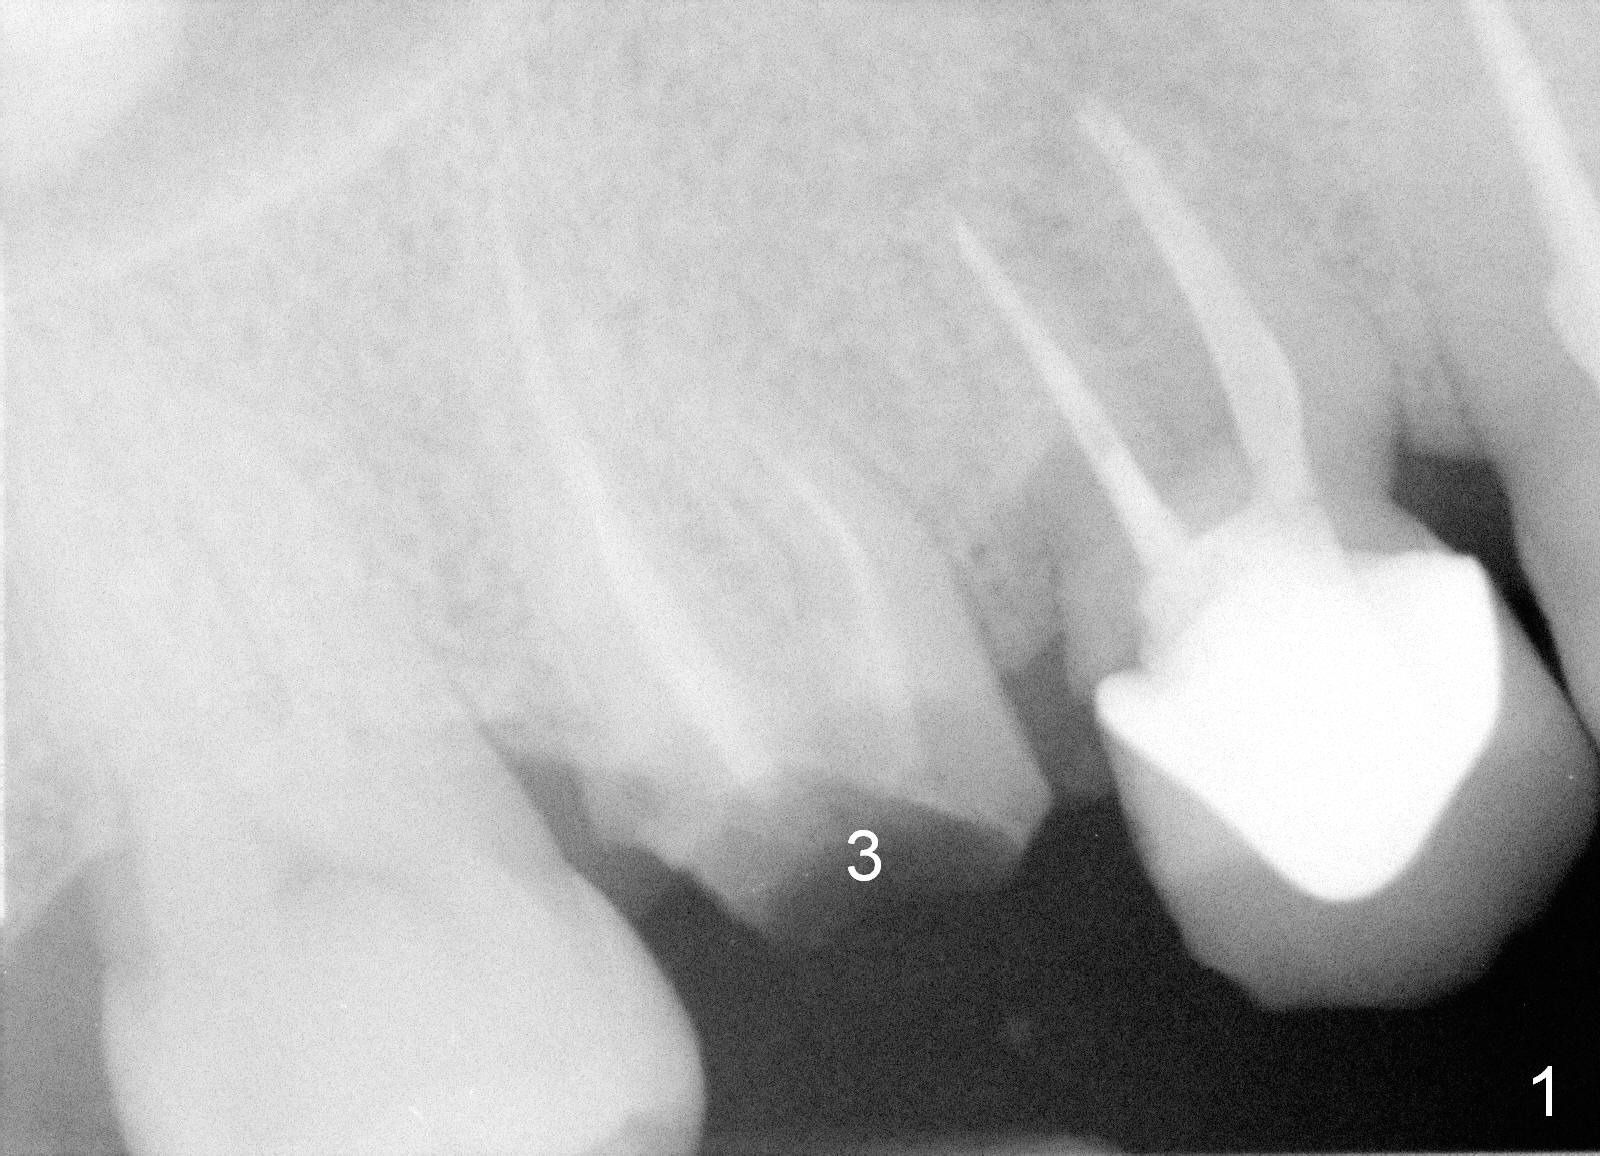

A 47-year-old man has multiple restoration. The crown of the tooth #3 has been recemented several times in the last 3 years (Fig.1). Before placement of an immediate implant at #3 (Fig.2), the root of the adjacent tooth is diagnosed to have crack and replaced by an immediate implant (Fig.3).

The last time the tooth #3 crown was recemented, there was caries in the remaining root stump. The tooth is deemed non-salvageable. The roots will be sectioned prior to extraction. There is no sign of periodontal disease. The bone is expected to be dense. It should be easier to use reamers for osteotomy than expanders or osteotomes. A relatively smaller implant should be able to achieve primary stability in the septum (Fig.4, as compared to Fig.2). The deeper portion of the sockets will be filled with collagen plug, while bone graft is used to cover exposed implant threads. If the 17 mm long implant has questionable stability, longer one will be placed (Fig.5). A 5x5 mm abutment will be most likely used for the shorter implant, whereas a shorter abutment for the longer implant.